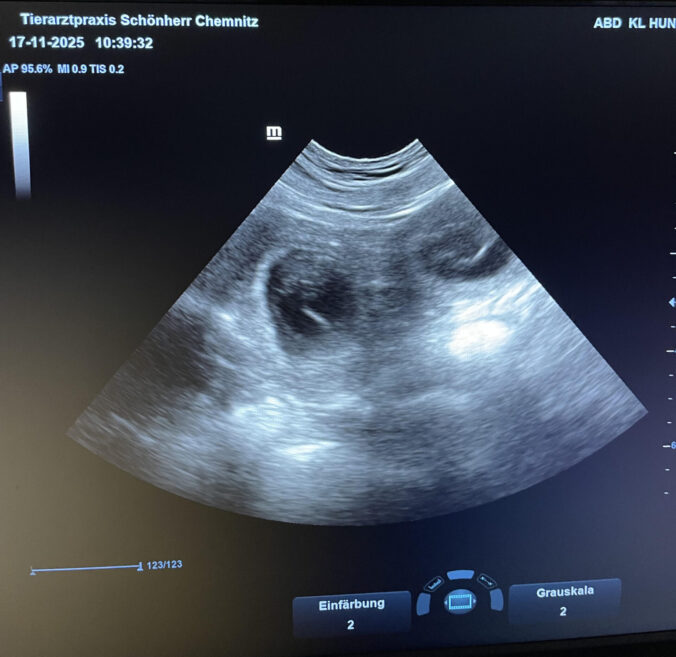

Die Tierärztin Franziska Schönherr (Chemnitz) konnte am 17.11.2025 die Trächtigkeit per Ultraschall bestätigen.

Wenn alles gut geht, erwarten wir zur Weihnachtszeit gelbe und schwarze Welpen. Wir sind überglücklich und freuen uns auf die Zeit!